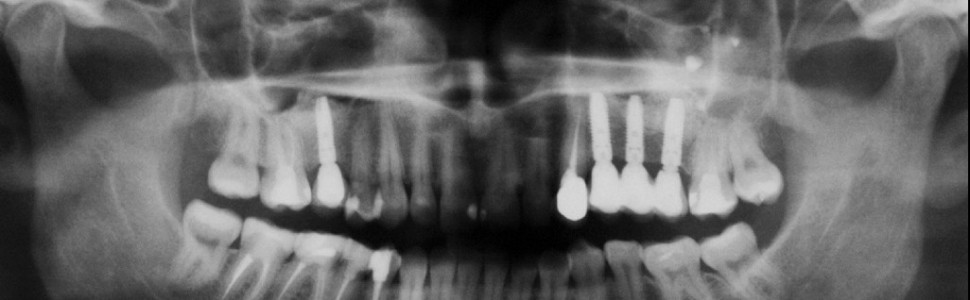

Odcinek boczny szczęki to obszar o niedostatecznych parametrach dotyczących ilości i jakości tkanki kostnej. Ponadto w tej okolicy występuje zatoka szczękowa, która po utracie uzębienia powiększa swoją objętość kosztem wyrostka zębodołowego. Wiąże się to z dodatkowymi utrudnieniami w leczeniu implantologicznym w tym odcinku.

W artykule przestawiono istotne zagadnienia dotyczące anatomii zatoki szczękowej, które mogą mieć wpływ na przebieg zabiegów chirurgicznych i ewentualne powikłania. Szczegółowo opisano techniki podniesienia dna zatoki metodą zamkniętą i otwartą oraz ich skuteczność. Przedstawiono rodzaje materiałów stosowanych do augmentacji dna zatoki. Omówiono również alternatywne rozwiązania implantologiczne, takie jak podniesienie dna zatoki szczękowej bez użycia materiałów wypełniających oraz zastosowanie wszczepów jarzmowych.

Zabieg podnoszenia dna zatoki wykonywany metodą otwartą z dojścia bocznego